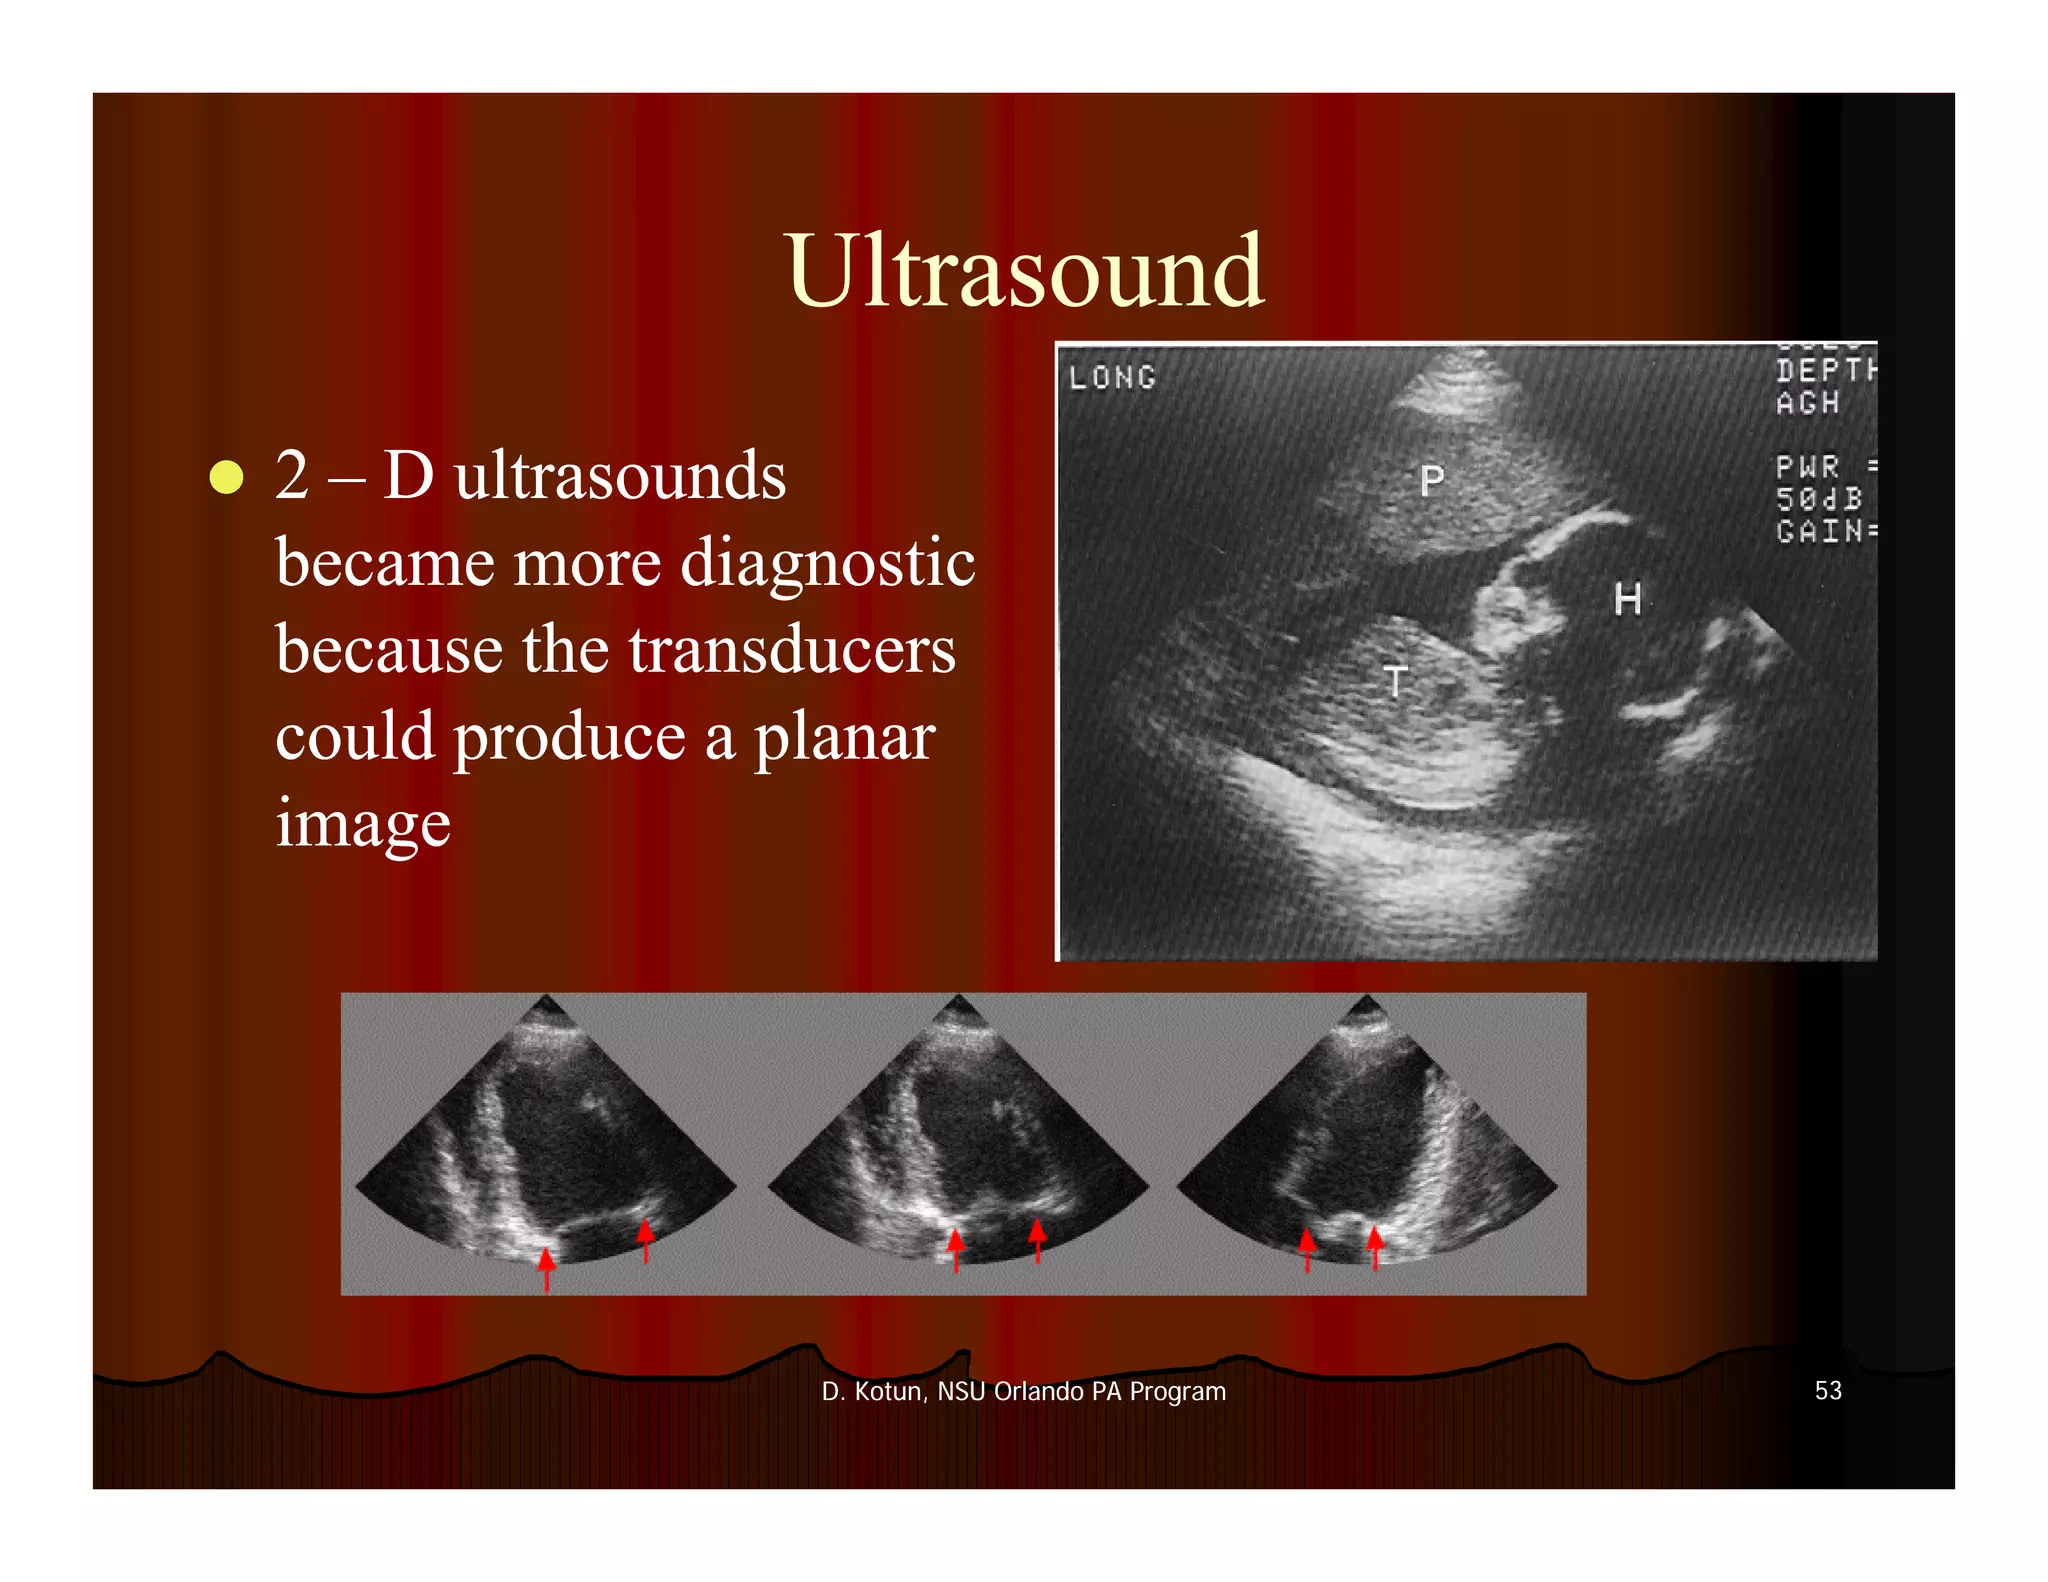

This document provides an introduction to various medical imaging modalities including X-ray, CT, mammography, MRI, PET, SPECT, and ultrasound. It discusses the principles, techniques, and indications for each modality. Key terms are defined. Images demonstrate examples of each type of imaging. The objectives are to recognize imaging study types, discuss how images are produced, list common indications, and describe imaging precaution considerations.